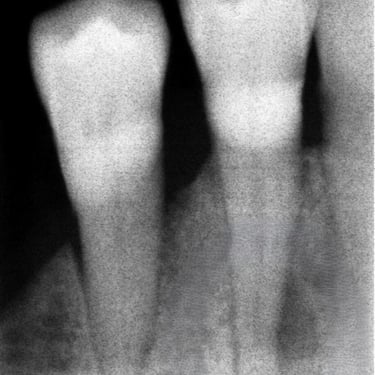

Hipercementosis

La hipercementosis es un engrosamiento anormal del cemento radicular del diente, a menudo debido a una inflamación crónica o trauma.

Los pacientes generalmente no tienen síntomas, pero la condición puede ser descubierta en una radiografía.

El tratamiento no suele ser necesario a menos que cause problemas con la extracción del diente.